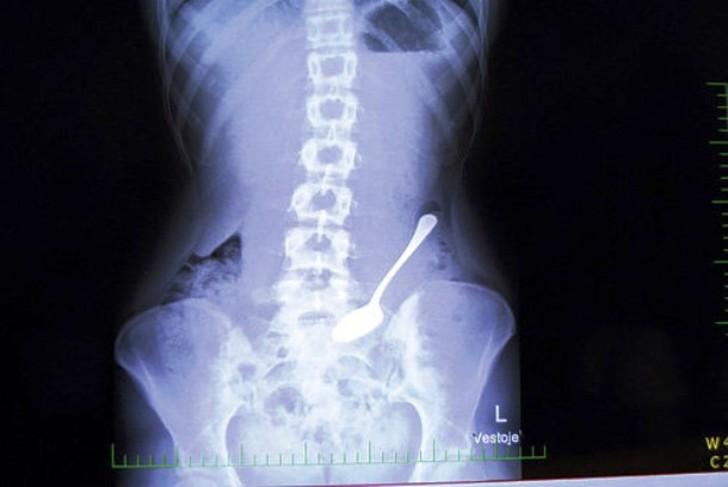

1. Ложка.